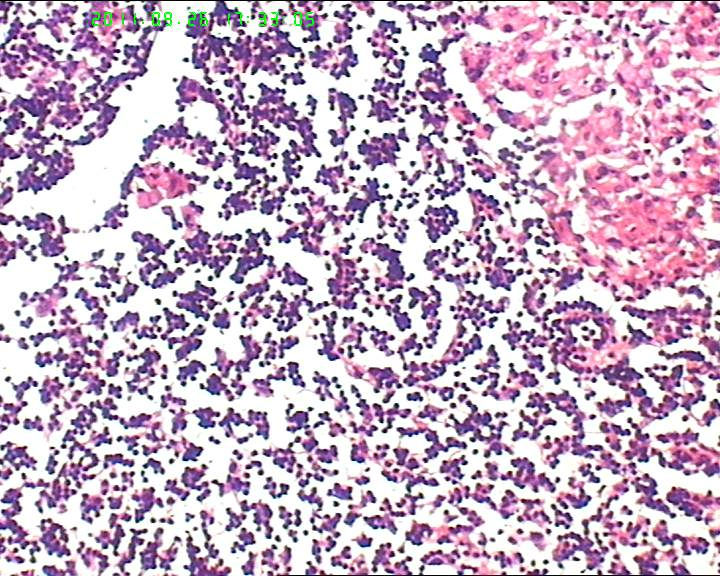

21岁女性左侧颌下淋巴结,该诊断什么?

灰白不整形肿物一个,大小3.5*2.5*2cm,包膜完整。

21岁女性左侧颌下淋巴结,该诊断什么?图1

慢性肉芽肿性炎症,形态学倾向结节病,但是作为病理工作者对于这样的病例,再结合咋们国情,还是建议临床除外增殖性结核后再考虑结节病。

肉芽肿性炎症,倾向结节病。